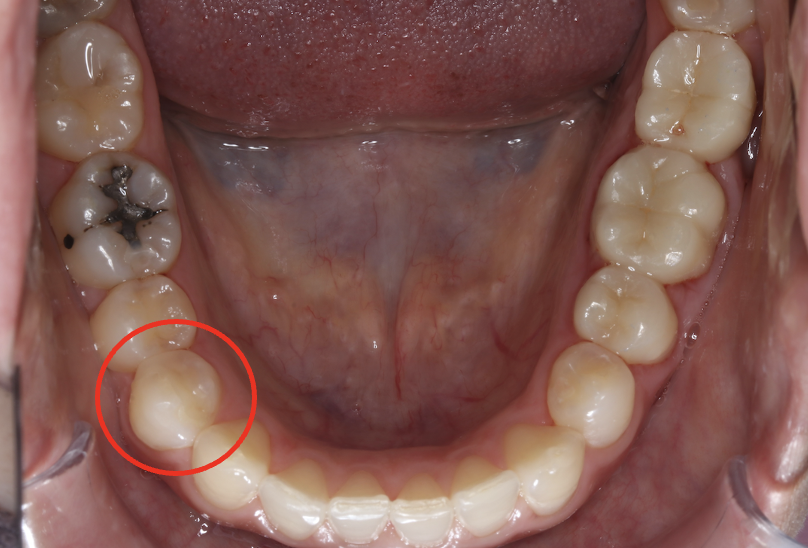

セラミック症例③

年齢30代女性

治療期間1ヶ月

治療内容セラミックインレー

治療箇所右下4番

治療費用100,000円